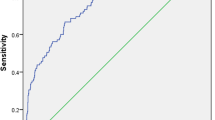

Multivariate logistic regression analysis

The variables with P < 0.05 in univariate logistic regression analysis were conducted for multivariate logistic analysis (Fig. 4). The independent risk factors of postoperative DVT in patients with femoral fracture included perioperative RBC infusion (P = 0.012), multiple traumas (P = 0.016), time from trauma to surgery > 7d (P = 0.002), time to start anticoagulation after surgery (P = 0.003), nephropathy (P = 0.015), hypoproteinemia (P = 0.000), COPD (P = 0.001), age (P = 0.002), the number of comorbidity (P = 0.000) and CRP level on day 3 after surgery (P = 0.005).